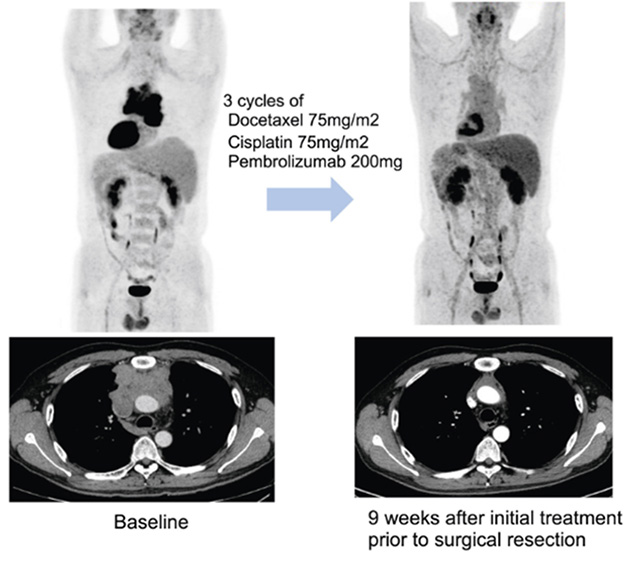

• 수술 전 3주 간격으로 세 차례 항암화학요법과 면역항암제 펨브롤리주맙을 병용한 뒤 종양이 감소한 환자의 영상 변화. 연구팀은 이 환자가 병리학적 완전관해에 도달했으며, 현재 3년 이상 재발 없이 경과 중이라고 밝혔다. /이미지 제공=삼성서울병원

▲ 수술 전 3주 간격으로 세 차례 항암화학요법과 면역항암제 펨브롤리주맙을 병용한 뒤 종양이 감소한 환자의 영상 변화. 연구팀은 이 환자가 병리학적 완전관해에 도달했으며, 현재 3년 이상 재발 없이 경과 중이라고 밝혔다. /이미지 제공=삼성서울병원